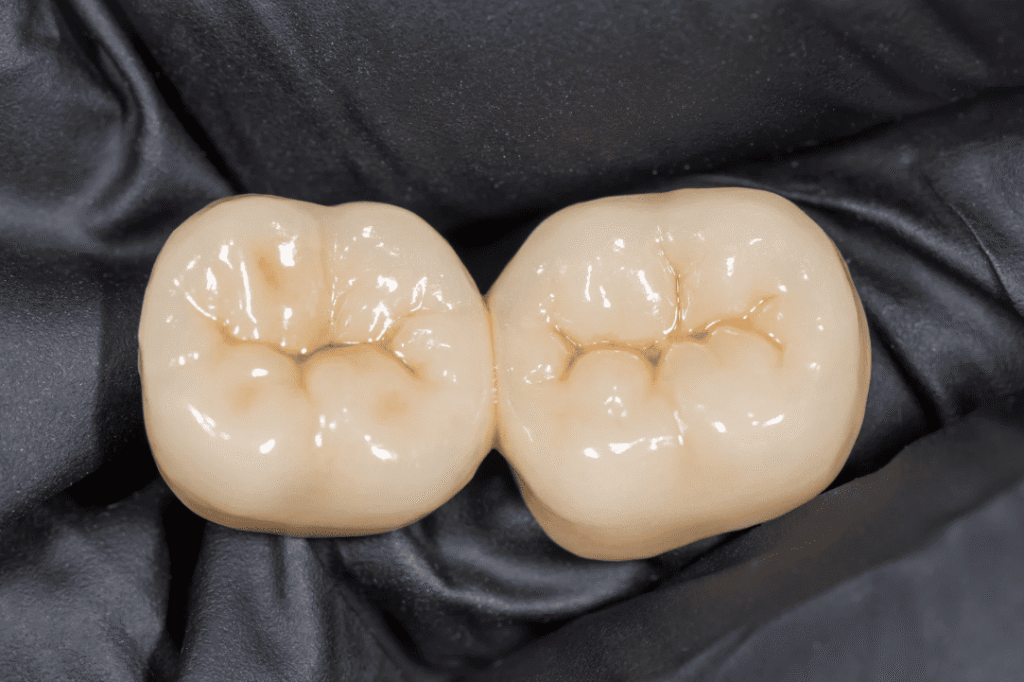

🦷 5. Dental Restoration

If bruxism has already caused tooth damage, restorative options include:

- Composite fillings

- Ceramic veneers

- Dental crowns

These treatments restore tooth shape, bite function, and aesthetics, ensuring both dental health and a confident smile.